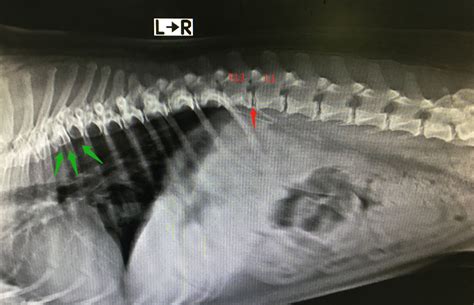

如果用B超声波检查的话,18天就可以探测出,甚至可分辨胎儿的性别,数量,妊娠后28到35天是最佳检查时间。X射线透视检查发,只能在40多天后进行,不能早期诊断。